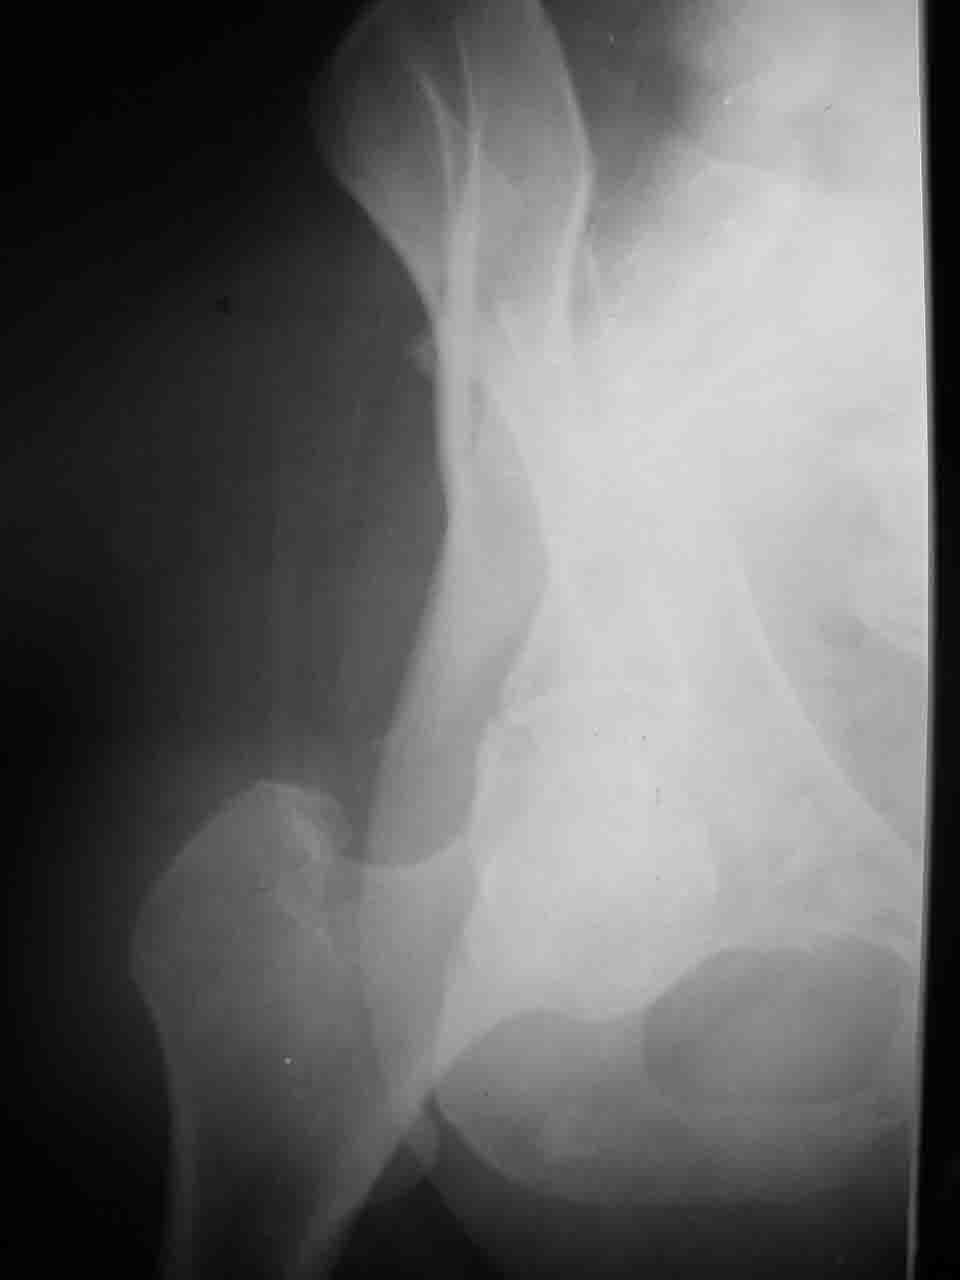

Логика подсказывает, что все-таки лучше иметь анатомически полноценную впадину, хотя ранее упоминалось состояние вторичной конгруэнтности и одно наблюдение у меня есть, когда у больного с полностью нарушенной анатомией впадины и подвывихом головки бедра кзади и кверху боли отсутствовали при относительно достаточном для стиля жизни больного объёме движений. Но это только одно наблюдение и кроме перелома впадины у этогобольного была и тяжелая ЧМТ в анамнезе. Основываясь на формулировке структуры ацетабулюм Э. Летурнеля - как перевернутой буквы Y, впадина для полноценной функции сустава должна иметь сферичность, соответствующую размеру головки бедра и если один из компонентов в дефиците, то функциональные последствия рано или поздно проявятся.

Сложностью, ассоциативностью характера перелома, я бы с радостью воспользовался мининвазивной перкутанной фиксацией винтами, но боюсь, что результат был бы ещё хуже, техникой непрямой репозиции перелома не владею, поэтому пытаясь получить анатомичную впадину приходится широко открывать, по крайней мере пока, а дальше буду пытаться уменьшать пространство...

Вопрос доступа к вертлужной впадине при остеосинтезе задача не простая. Конечно, у Летурнеля и Тайла всё давно описано, нам остается только брать на вооружение. Но сами понимаете, что не бывает двух одинаковых ситуаций, поэтому в каждом случае вопрос решается сугубо индивидуально. Наша главная цель - восстановить анатомию с нанесением минимальной дополнительной травмы тазобедреннному суставу, думаю с этим никто не поспорит. Расширенный илиофеморальный доступ уж слишком травматичен (как сказал один коллега "таз лежит отдельно, больной отдельно").Стоит ли делать из пациента анатомический препарат для того чтобы легче ориентироваться. Да и нужно ли собирать всю "мозаику"? Мы применяли при таких операциях своеобразную операционную хитрость - сначала устраняли грубое смещение крыла под гребнем с фиксацией так называемой "плавающей" пластиной (временно фиксированной на двух винтах)- доступ или продлевали боковой, или делали небольшой дополнительный разрез над гребнем. Это позволяло устранить грубое смещение и захождение отломков тела повздошной кости, что значительно облегчало репозицию и остеосинтез впадины над сводом. Основное внимание конечно же уделяли нагружаемому задне-верхнему отделу. Сообщите ваш адрес, пришлю схемы и рентгенограммы.